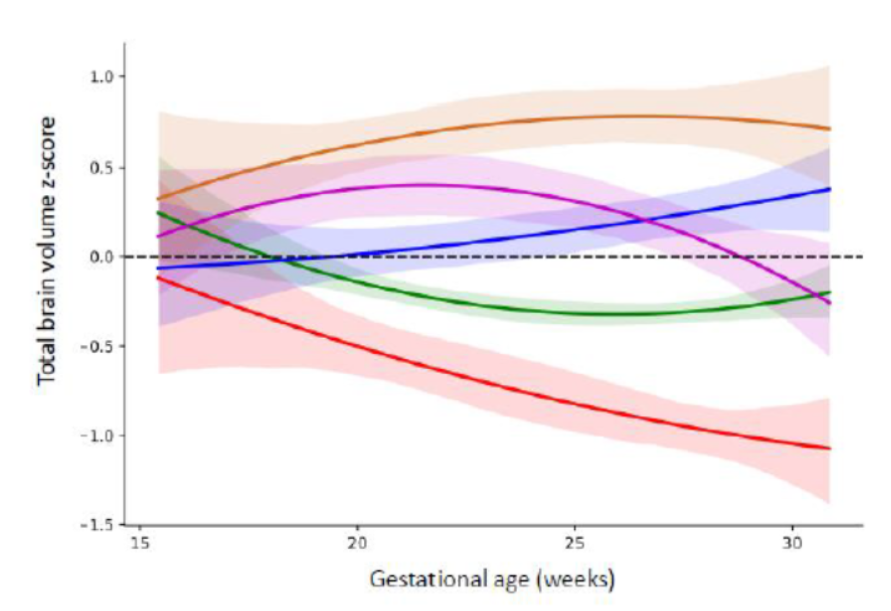

Normative spatiotemporal fetal brain maturation with satisfactory development at 2 years

Normative growth trajectories of fetal brain regions validated by satisfactory maturation of neurodevelopmental domains at 2 years of age

Normative spatiotemporal fetal brain maturation with satisfactory development at 2 years